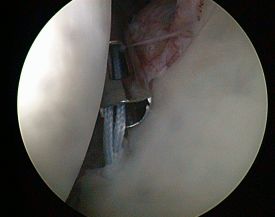

HD-Bilder aus dem Schulter- und Kniegelenk

- zielgenaue Behandlung (gute Sicht dank stark vergrößerter Gelenkdarstellung über HD-Monitor)

Schultergelenk

- Naht beim Sehnenriss der Rotatorenmanschette

- Annähen der Schulterpfannenlippe nach Riss infolge von Verrenkungen

- Stabilisierung des Schultergelenkes